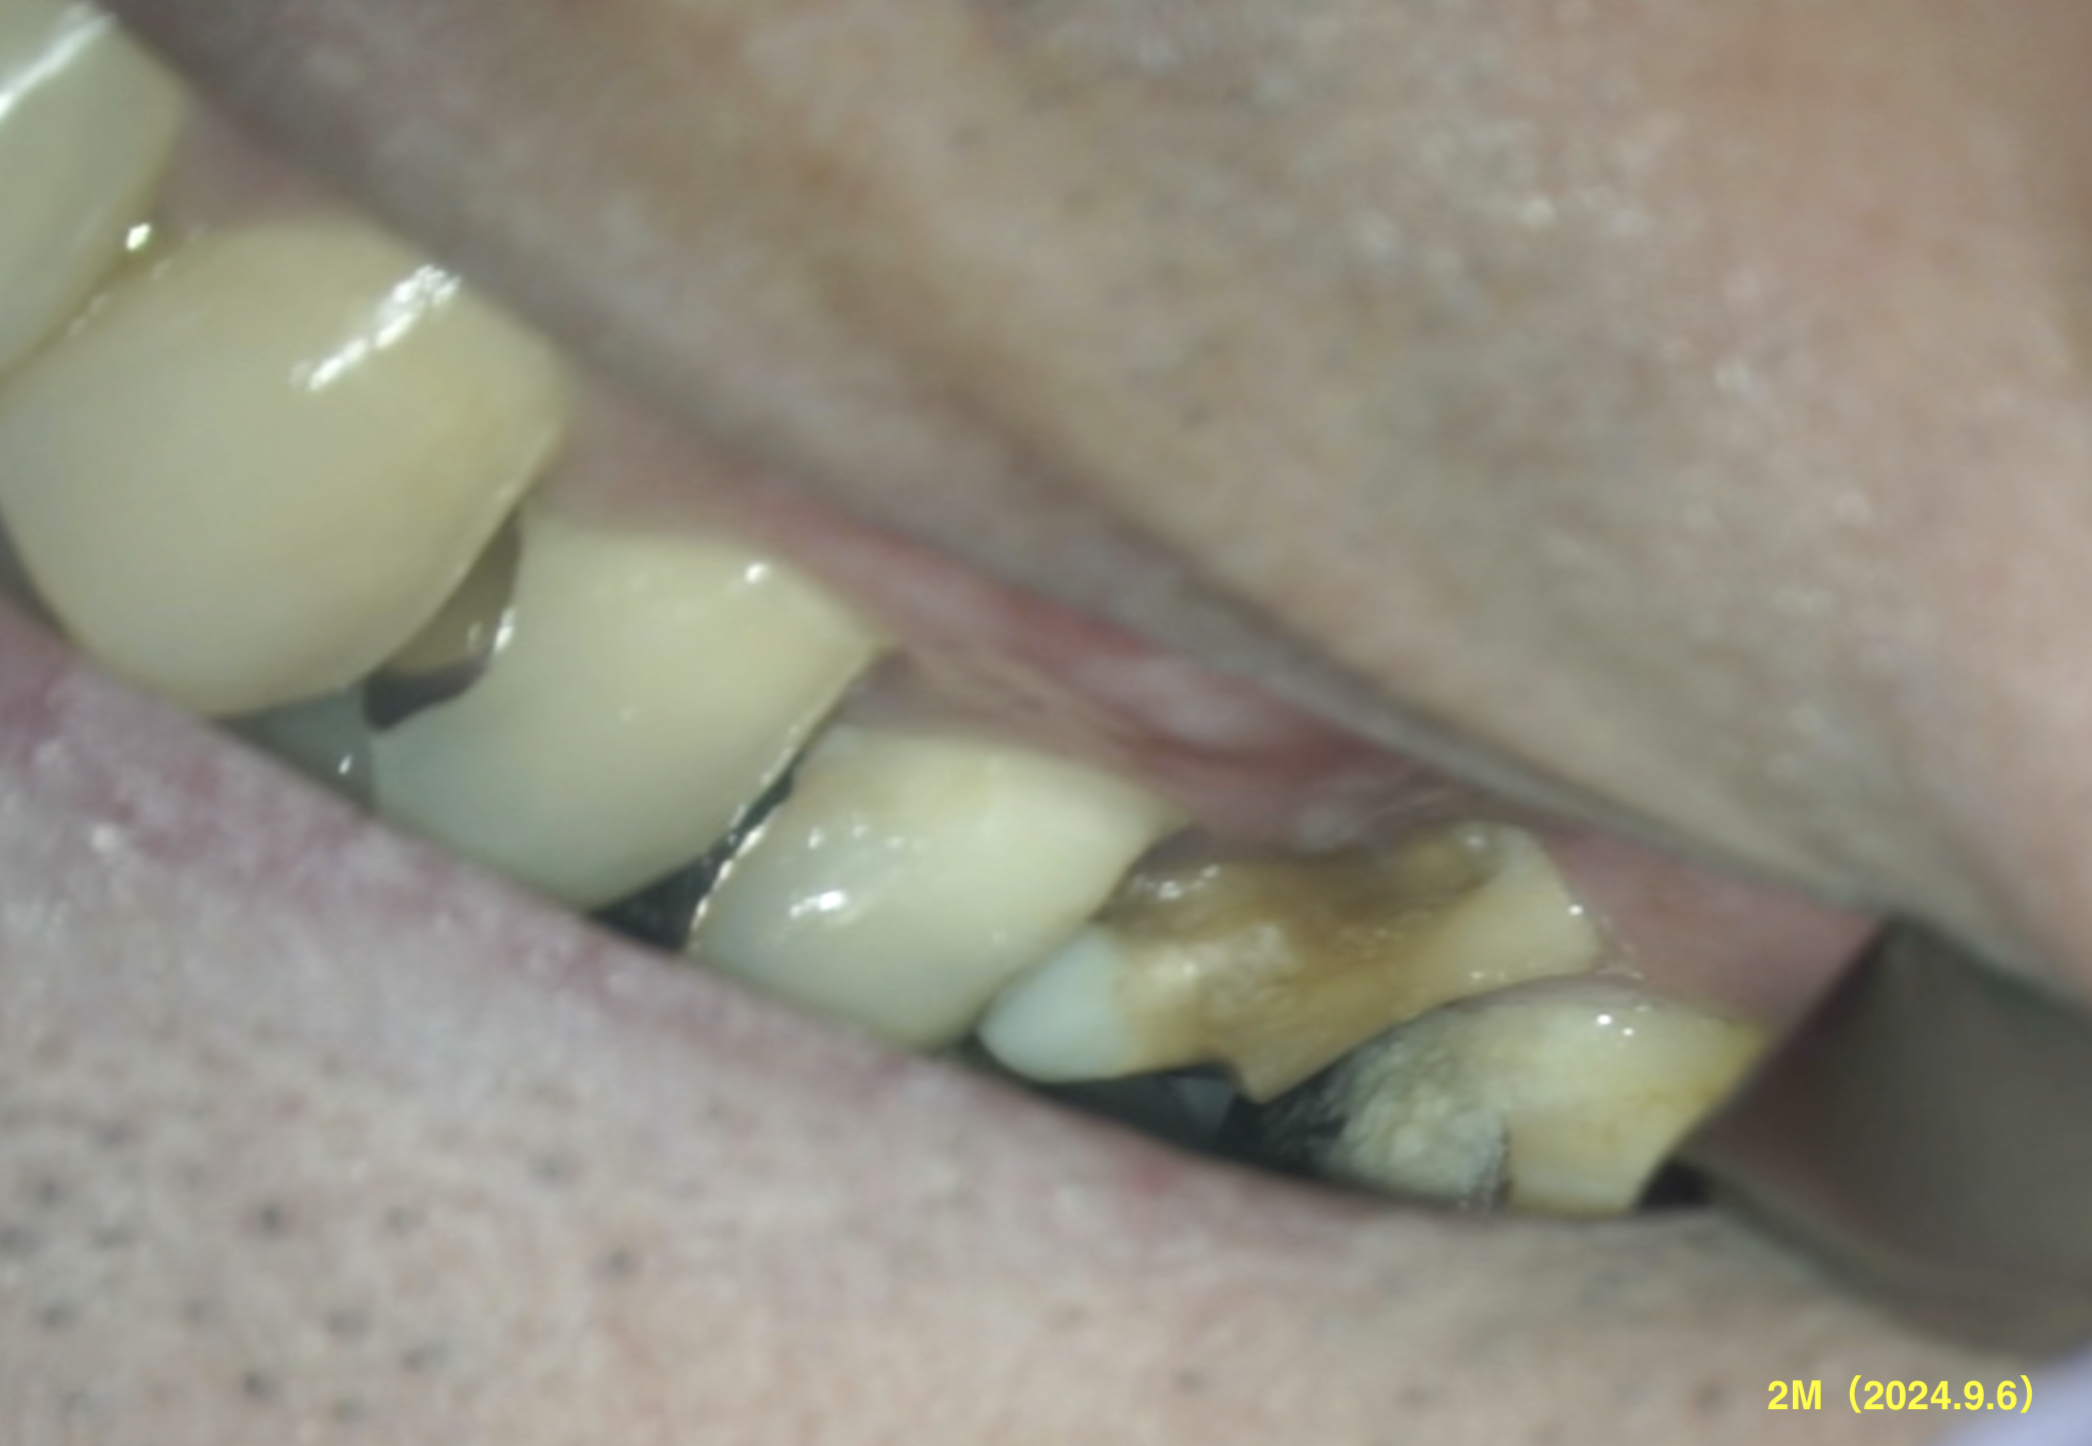

この2ヶ月後にRecallするのだが、

臨床症状は消失したが、口腔内の清掃は悪く歯肉はリセッションしていた。

この時点で歯肉移植も困難だ、と言う話を歯周病専門医からは指摘された。